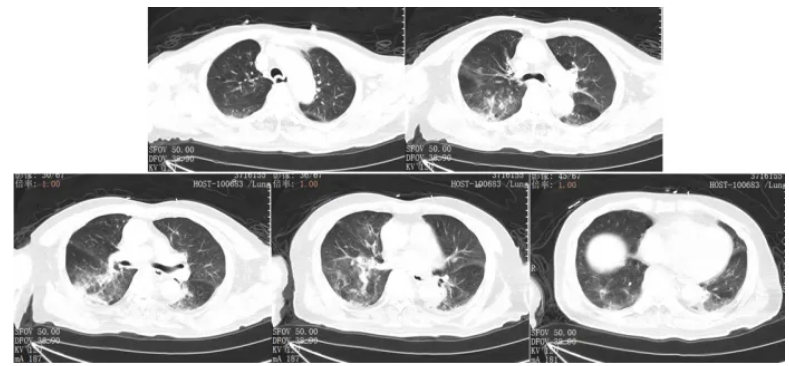

根据病原回报结果,1月13日停用美罗培南。因伏立康唑血药浓度偏高且肾功能恶化,将原研伏立康唑针改为口服伏立康唑片0.2 g q12h;加用更昔洛韦针0.2 5 g q12h针对人类α疱疹病毒1型);针对纹带棒杆菌加用利奈唑胺针0.6 g q12h;1月17日患者复查肺部CT提示双肺感染面积较前明显增加,少许胸腔积液并伴有肺不张(图5)。

图5 复查胸部CT(2025-01-17)